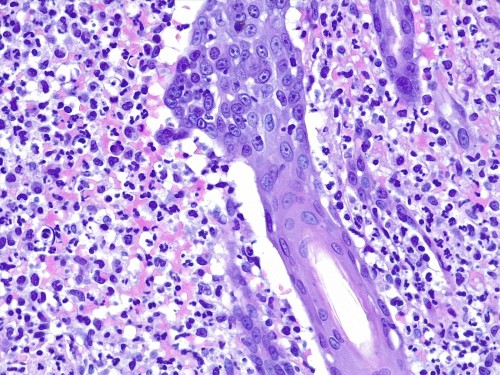

– les biopsies cutanées (LAPVSO) concluent à de sévères lésions de dermohypodermite neutrophilique avec furonculose et lésions hypodermiques ponctuelles de vascularite leucocytoclasique (Photos 4 à 9)

Examen histopathologique montrant un épiderme intact ou sévèrement ulcéré. Dans le derme, on observe un œdème superficiel ainsi que de multiples foyers inflammatoires non encapsulés, souvent à point de départ folliculaire ou périfolliculaire, pouvant fusionner, rompre les follicules pileux et s’étendre dans l’ensemble du derme voire gagner l’hypoderme. Ces foyers sont caractérisés par l’accumulation de granulocytes neutrophiles qui semblent altérés et qui dissèquent les fibres de collagène autour du follicule pileux ainsi que la paroi folliculaire et la lumière folliculaire. De nombreuses plages inflammatoires contiennent des tiges pilaires nues. L’infiltrat peut s’étendre dans l’hypoderme, mais ce dernier est surtout caractérisé par un épaississement des septa conjonctifs interlobulaires du tissu adipeux avec œdème, accumulation d’un matériel fibrinoïde, dilatation vasculaires des vaisseaux lymphatiques et des structures vasculaires de petit calibre, les vaisseaux lymphatiques étant encombrés d’un matériel inflammatoire fibrino-leucocytaire. Il peut exister des images focales de vascularite leucocytoclasique au sein de l’hypoderme.